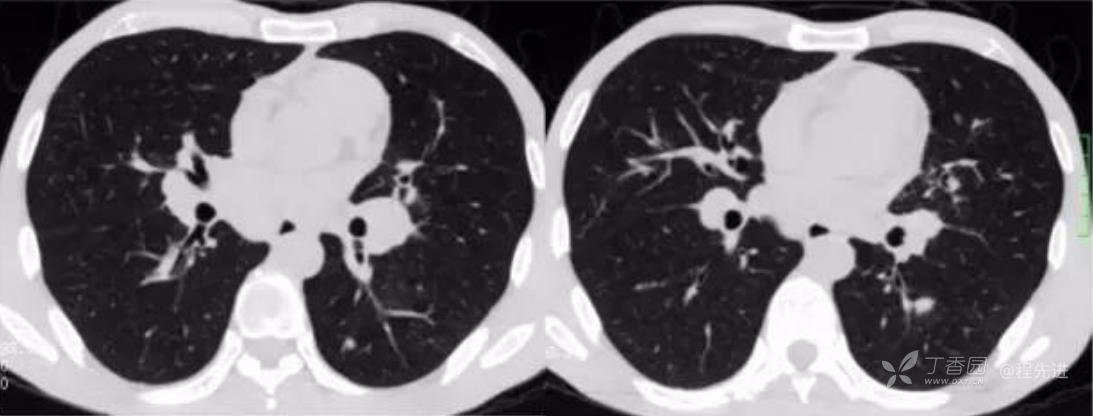

平扫纵隔窗